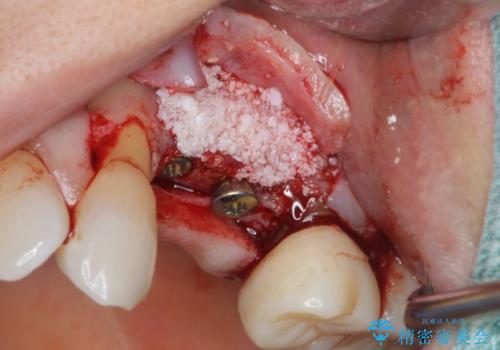

歯の穿孔(内部穴が開いている状態)破折等、歯を保存することができない問題が小臼歯には認められたので抜去を行います。

抜去後の補綴治療は長いブリッジではなくインプラント治療を希望されましたが、穿孔・破折による周囲の骨吸収をリカバリーすべく骨の造成を伴うインプラント治療を計画します。

インプラント治療を行うにはインプラント周囲に十分な骨の幅・高さが必要です。

今回はが原因で失われてしまった骨の幅を回復することで長期的な予後を見込めるインプラント治療を行うことができました。